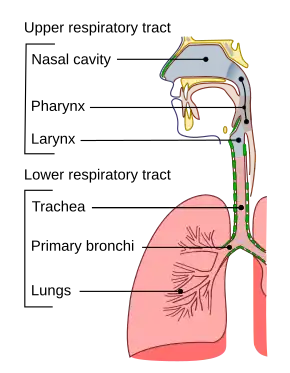

The nasal cavity is a large , air-filled space above and behind the nose in the middle of the face. The nasal septum divides the cavity into two cavities,[1] also known as fossae.[2] Each cavity is the continuation of one of the two nostrils. The nasal cavity is the uppermost part of the respiratory system and provides the nasal passage for inhaled air from the nostrils to the nasopharynx and rest of the respiratory tract.

The floor of the nasal cavities, which also form the roof of the mouth, is made up by the bones of the hard palate: the horizontal plate of the palatine bone posteriorly and the palatine process of the maxilla anteriorly. The most anterior part of the nasal cavity is the nasal vestibule.[4] The vestibule is enclosed by the nasal cartilages and lined by the same epithelium of the skin (stratified squamous, keratinized). Within the vestibule, this changes into the typical respiratory epithelium that lines the rest of the nasal cavity and respiratory tract. Inside the nostrils of the vestibule are the nasal hair, which filter dust and other matter that are breathed in. The back of the cavity blends, via the choanae, into the nasopharynx.

The nasal cavity is divided into two segments: the respiratory segment and the olfactory segment.

- The respiratory segment comprises most of each nasal cavity, and is lined with ciliated pseudostratified columnar epithelium (also called respiratory epithelium). The conchae, or turbinates, are located in this region. The turbinates have a very vascularized lamina propria (erectile tissue) allowing the venous plexuses of their mucosa to engorge with blood, restricting airflow and causing air to be directed to the other side of the nose, which acts in concert by shunting blood out of its turbinates. This cycle occurs approximately every two and a half hours.

The two nasal cavities condition the air to be received by the other areas of the respiratory tract. Owing to the large surface area provided by the nasal conchae (also known as turbinates), the air passing through the nasal cavity is warmed or cooled to within 1 degree of body temperature. In addition, the air is humidified, and dust and other particulate matter is removed by nasal hair in the nostrils. The entire mucosa of the nasal cavity is covered by a blanket of mucus, which lies superficial to the microscopic cilia and also filters inspired air. The cilia of the respiratory epithelium move the secreted mucus and particulate matter posteriorly towards the pharynx where it passes into the esophagus and is digested in the stomach. The nasal cavity also houses the sense of smell and contributes greatly to taste sensation through its posterior communication with the mouth via the choanae.